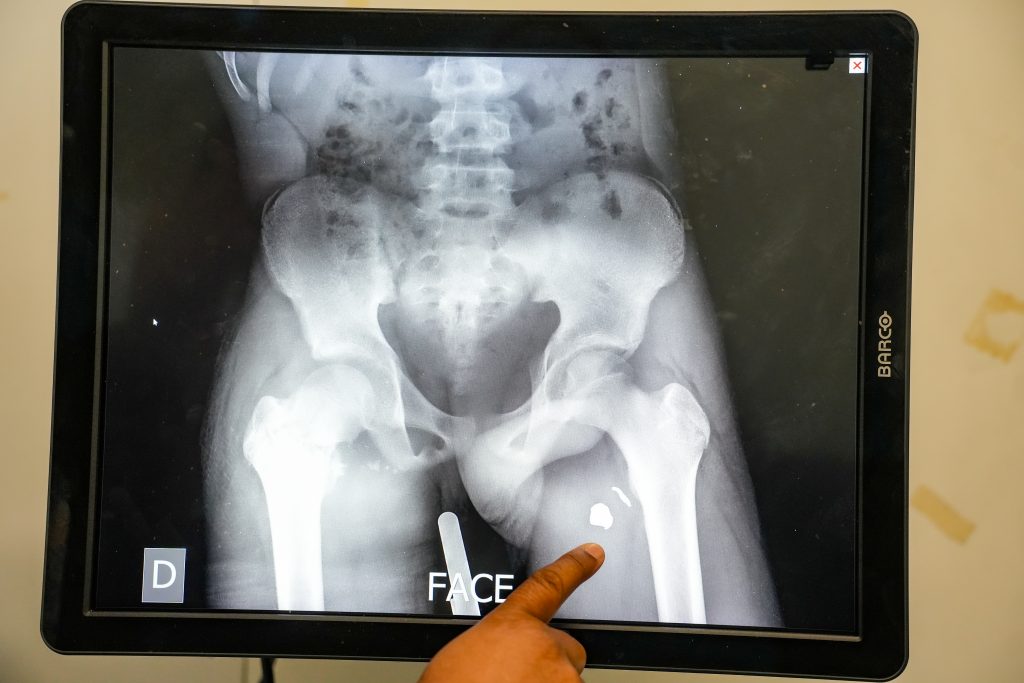

Despite these severe constraints people face trying to access care, MSF has recorded a marked increase in violence-related admissions at our Drouillard hospital. Between Dec. 29, 2025, and Jan. 12, 2026, 101 patients injured by violence were admitted in just 15 days, including 66 with gunshot wounds. This two-week figure already far exceeds the monthly average of 54 gunshot wound admissions at Drouillard in 2025. Of these patients, 30 per cent were women and nine per cent were children under 15.

Patients requiring surgical care are referred to Tabarre trauma hospital, one of the last facilities in the capital still able to provide free specialized surgical care. These referrals, however, occur under precarious conditions. For over a year, MSF has had to suspend our ambulance service due to repeated threats and attacks on vehicles and patients during transfers between medical facilities. Some vehicles from the state ambulance center remain operational, but their capacity is insufficient. As a result, many critically injured patients arrive late, after fighting has subsided in their neighbourhoods, often transported by non-medical means such as mototaxis.

In 2025, 686 patients injured by violence were admitted to MSF’s Tabarre hospital, nearly 90 per cent of them with gunshot wounds. Among those shot were 193 women and 47 children under 14. The trend shows no sign of slowing: on Jan. 6, 2026, alone, MSF admitted eight patients with gunshot wounds in a single day, highlighting the persistence and intensity of violence in the capital.